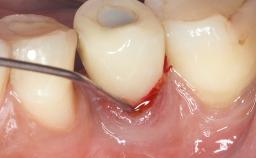

Treatment of Peri-Implantitis at a Zirconia Implant

Frank Schwarz, Ausra Ramanauskaite

Due to their promising clinical performance, zirconia implants have recently become popular alternatives to titanium implants, particularly for areas with high esthetic demands (Holländer and coworkers 2016; Roehling and coworkers 2016; Lorenz and coworkers 2019). However, regardless of the reported high survival and success rates, zirconia implants were affected by peri-implant diseases over the short observation period, suggesting the importance of treating peri-implant diseases at zirconia implants (Becker and coworkers 2017). In their case, Frank Schwarz and Ausra Ramanauskaite present 3-year results following mechanical debridement alongside Er:YAG laser monotherapy.